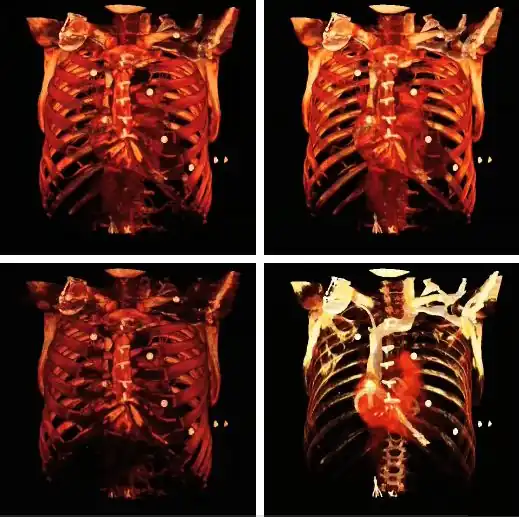

Volume rendering can be applied to the voxel data in the successive rotation manner described for MIPs above, as illustrated by the results in the following figure:

Note that the volume rendering can be contrast enhanced so as to threshold, for instance, through the voxel values to eliminate low attenuating surfaces, as illustrated in the following figure:

Note also that the colour look-up table (CLUT) can be varied to highlight features of particular interest, as shown in the set of images below:

The influence of the opacity table is illustrated in the following example images:

The influence on volume rendering of various shading settings is shown below:

The shading settings used for the above images are as follows:

| Image | Ambient Coefficient | Diffuse Coefficient | Specular Coefficient | Specular Power |

|---|---|---|---|---|

| Top Left | 0.15

|

0.9

0.3

15.0

| Top Middle | 0.75

| Top Right | 0.15

0.1

| Bottom Left | 0.15

1.2

| Bottom Middle | 0.15

1.0

| Bottom Right | 0.15

0.6